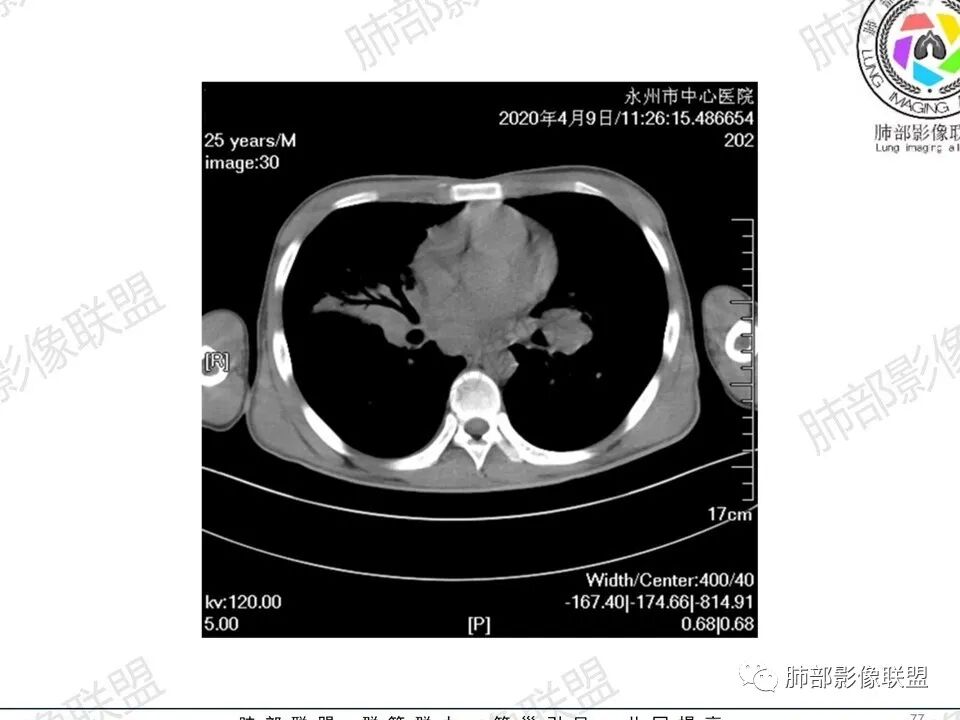

3、影像表现:双肺散在斑片影及结节影,部分结节内可见血管穿行,斑片影沿支气管血管束分布,近胸膜侧病变收缩不明显。部分中央淋巴间质增厚,小叶间隔增厚。病灶内支气管穿行,部分支气管略扩张。局部小结节呈串珠样改变。纵隔、肺门区、锁骨上及腋窝淋淋巴结肿大,部分有融合。心腔低密度。脾大。

5.双肺门及纵隔淋巴结显著增大,这改变相当显眼。这里强调“双肺门”及“多发”!

增大的淋巴结密度偏低且均匀。此外患者有体表淋巴结增大。

7.脾脏增大。

1.临床表现明显,纵隔及双肺门淋巴结显著肿大,临床最为担心的还是淋巴瘤!

尤其患者有贫血及脾脏增大,又有体表淋巴结增大时,这也是临床相对常见的情形。

淋巴瘤肺部浸润表现多样,多发结节影是其最常出现的影像学改变,尤其是霍奇金病。

2.右肺多发微小结节影,部分沿血管束分布,尽管未见小叶间隔改变,但双肺门淋巴结增大确实应当首先排除结节病,但经验上说,结节病的增大淋巴结密度往往较高、较密实,边界往往清楚,“独立性”很强,绝无“融合之嫌”!此外,较少出现贫血、脾大,临床表现也往往较轻微。